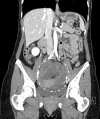

Covid no-related surgical emergencies during Covid-19 time. Case report: broad ligament internal hernia with associated small bowel necrosis